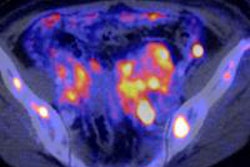

This 62-year-old melanoma patient has a 10-mm metastasis in the right upper lobe. The CT image (left) failed to show increased tracer uptake on the F-18 FDG PET image (right). All images courtesy of Dr. Marius Mayerhoefer.

The same patient as seen with the fused color-coded PET/CT image.F-18 FDG PET can help in the workup of pulmonary nodules because it reflects the tissue glucose metabolism, which is elevated in most malignant lung lesions. But mainly due to its limited spatial resolution, the sensitivity of PET for detecting pulmonary metastases is only moderate: In melanoma patients, it is between 57% and 70%, according to Mayerhoefer.